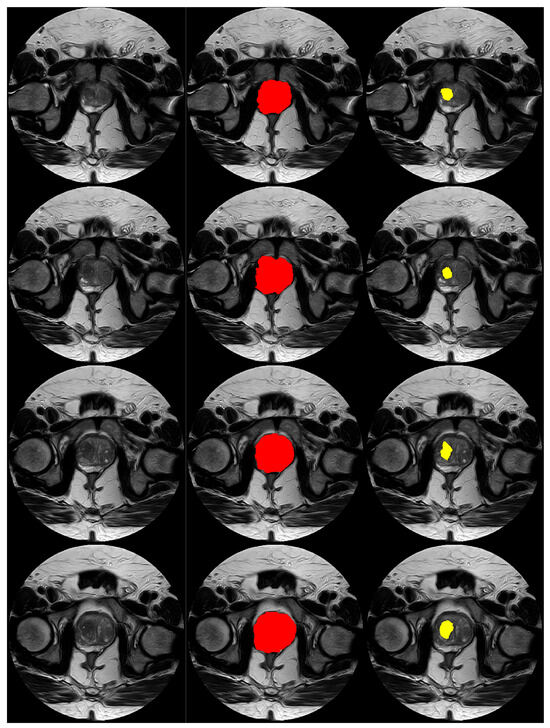

Further, Figure 6 and Figure 7 display visual examples of the segmented sections for the prostate and lesion of two test cases. In the images, the left column represents the scan, the middle column represents the prostate, and the right column represents the lesion.